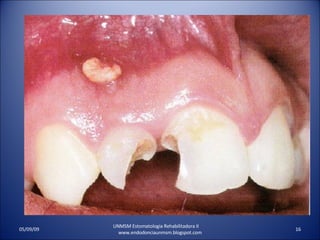

ABSCESO PERIRRADICULAR AGUDOINFLACION DEL PLIEGUE MUCOBUCAL Y TEJIDOS FACIALES . PRESENCIA DE FIEBRE- SENSIBILIDAD DE LOS GANGLIOS LINFATICOS CERVICALES Y SUBMAXILARES- UNMSM Estomatologia Rehabilitadora II www.endodonciaunmsm.blogspot.com 06/10/09

ABSCESO PERIRRADICULAR CRONICONO RESPONDE A LA PRUEBA DE VITALIDAD PULPAR. RX. RADIOLUCIDEZ PERIRRADICULAR. PIEZA DENTAL INSENSIBLE A LA PRESION. EL PACIENTE LO NOTA DIFERENTE. MUESTRA SUPURACION INTERMITENTE POR UN TRACTO SINUSAL ASOCIADO. UNMSM Estomatologia Rehabilitadora II www.endodonciaunmsm.blogspot.com 06/10/09